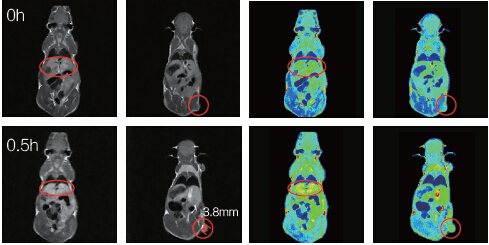

利用1T-MRI可以实现小鼠生理特征的定量计算,包括组织体积、肿瘤的尺寸、造影效果定量化评价等;MRI方法无需处死老鼠,简单快速,提高了实验结果的可靠性、实验速度与实验的连续性。

小鼠肿瘤直径3.8mm;打入新型Mn螯合造影剂0.5h之后,通过灰度平均值计算,发现肝脏与肿瘤造影明显。